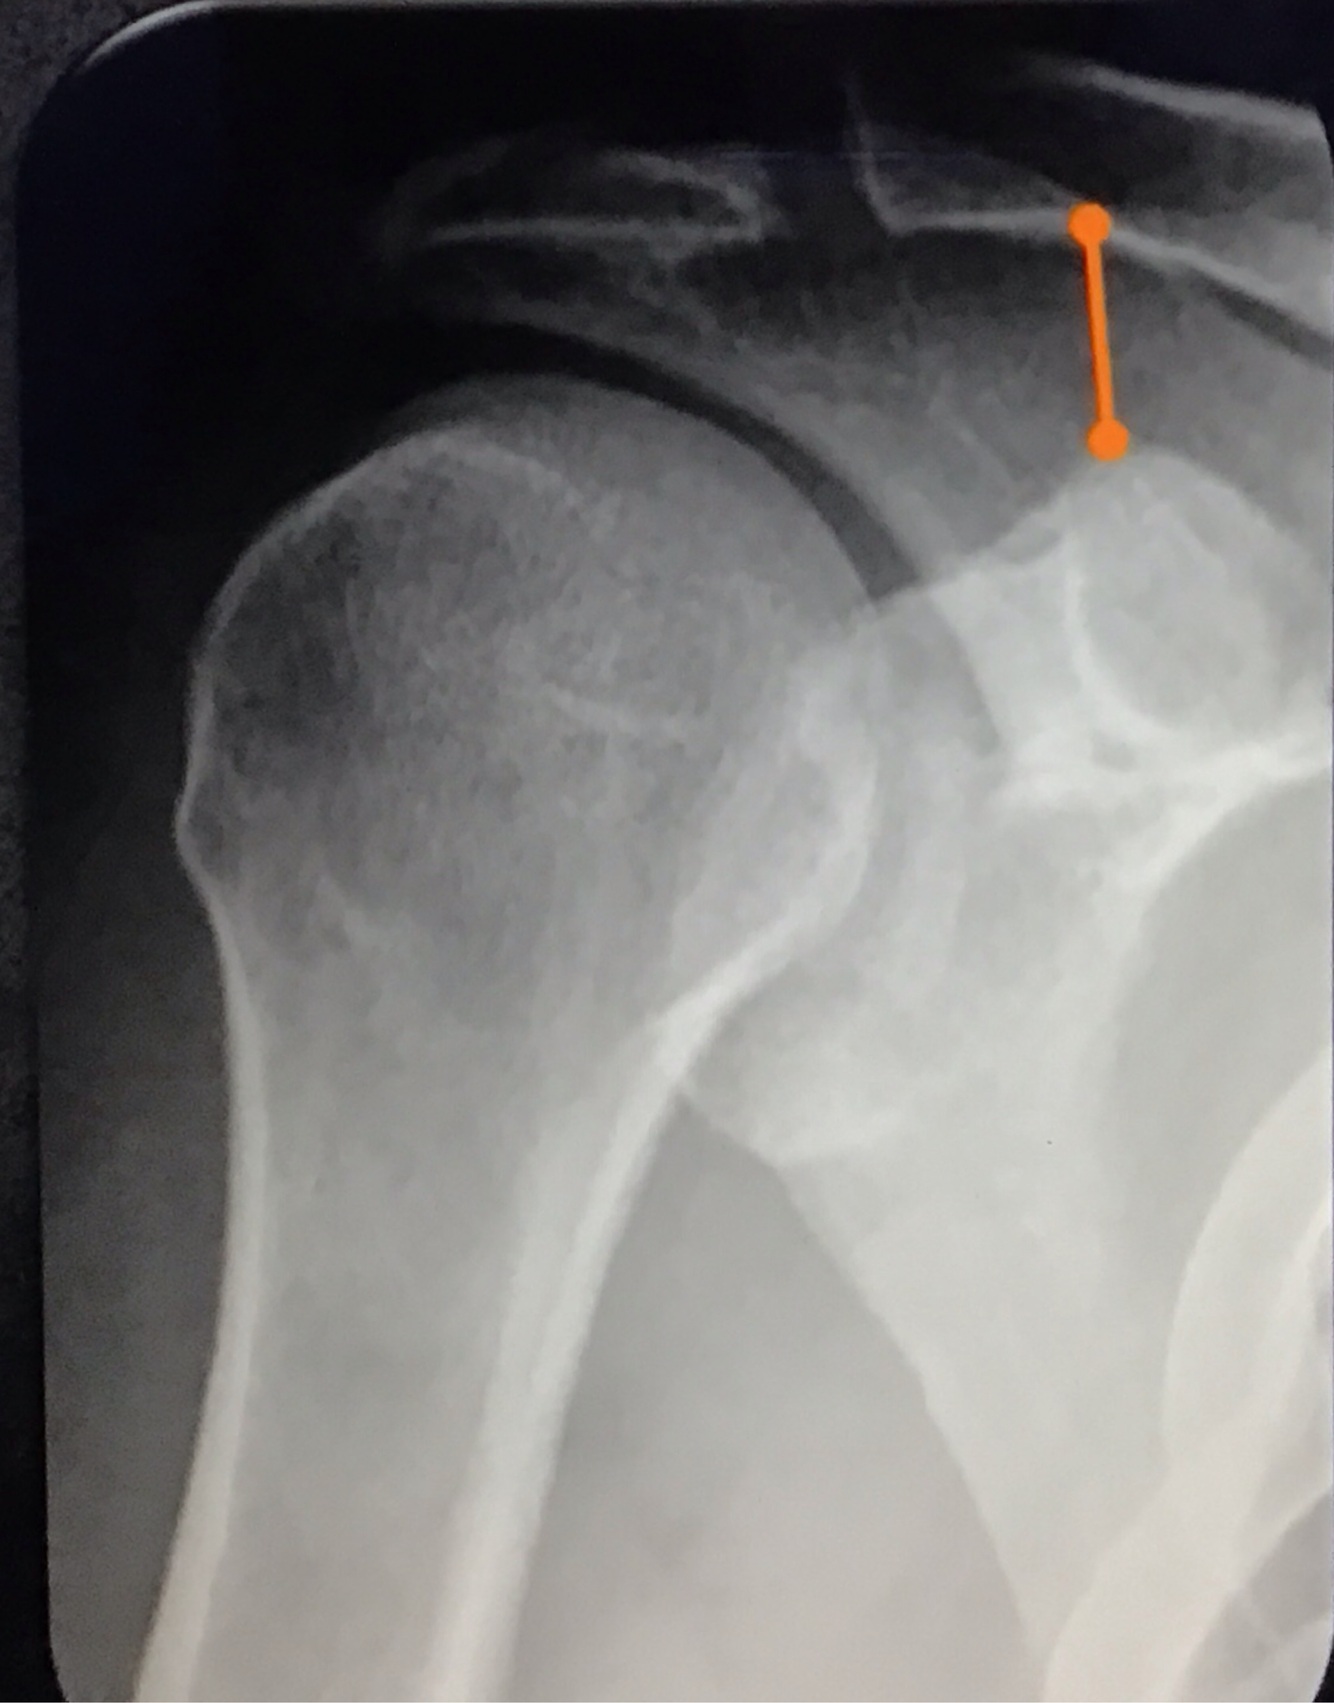

Qual a melhor incidência radiográfica pra avaliar LAC?

A

Zanca

angulação cranial de 10 a 15°

Qual a distância coracoclavicular normal?

11 a 13mm

Qual a distância acromioclavicular normal?

7mm nos homens

8mm nas mulheres